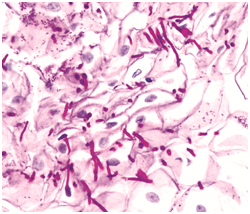

Figure 2 Periodic acid Schiff’s stain- Hyphae and spores.

Figure 3 Silver Methanamine (Grocott's stain)-Candida yeast and pseudohyphae.

Acute candidiasis: The distinguishing aspect is the presence of neutrophils in the stratum corneum. Disseminated disease expounds dermo-epidermal inflammatory infiltrate with intra-epithelial micro-abscesses.1,5 Fungal components are infrequent. Periodic acid Schiff(PAS), Silver Methanamine (Grocott stain- black fungal hyphae with a green environment and is specific for the deteriorating fungus ) aids in delineating the organism.1,5